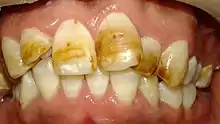

Fluorosis Leve - TF 4 (Moderado): Toda la superficie exhibe una marcada opacidad parecida al blanco tiza o gis, pudiendo estar acompañada de betas y manchas de color, desde amarillo a marrón, pudiendo aparecer partes desgastadas por atrición.

Fluorosis Moderada, Anomalía Dentaria de Estructura

Fluorosis Severa - TF 9 (Severo): Pérdida de superficie de esmalte que abarca un área mayor al 50%. El esmalte remanente es blanco opaco